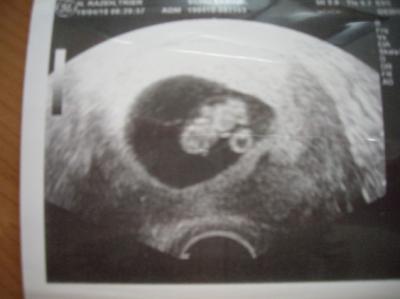

War heute morgen beim FA, alles in bester Ordnung. Krümel ist 2 cm groß. Nächsten Montag muss ich wieder hin, dann wird endlich mein Mupa erstellt. Hab mich auch heute auf der Arbeit geoutet. Bin froh, dass die Heimlichtuerei jetzt ein Ende hat Hab noch ein Bildchen von meinem Gummibärchen angehangen. Wurde heute bei 8+3 gemacht

Bild zu US-Bildchen - Forum für November - Mamis